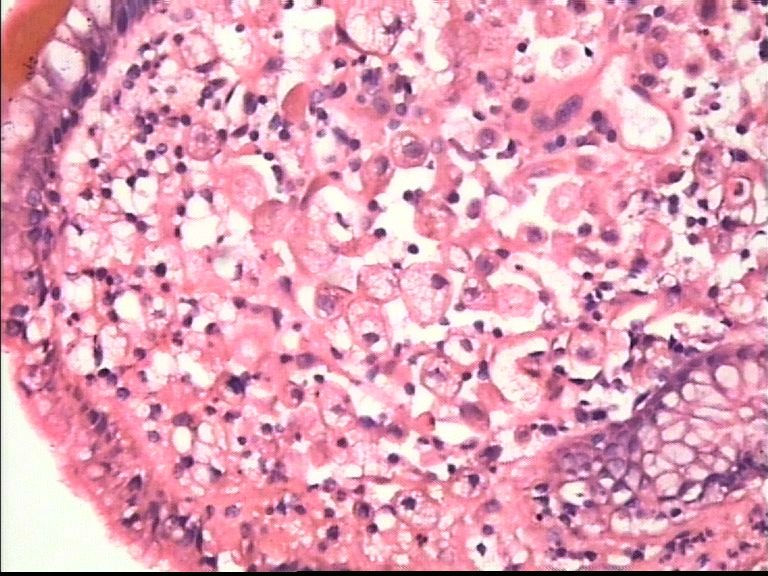

胃部溃疡3cm 53岁 男

• 胃部溃疡3cm 53岁 男图3

图3

仅此局部形态,应该是印戒细胞癌,最好有更多的背景资料

印戒细胞癌

倾向印戒细胞癌

诊断印戒细胞癌

印戒细胞癌高度可疑,建议做:CK、CD68、PAS帮助诊断。